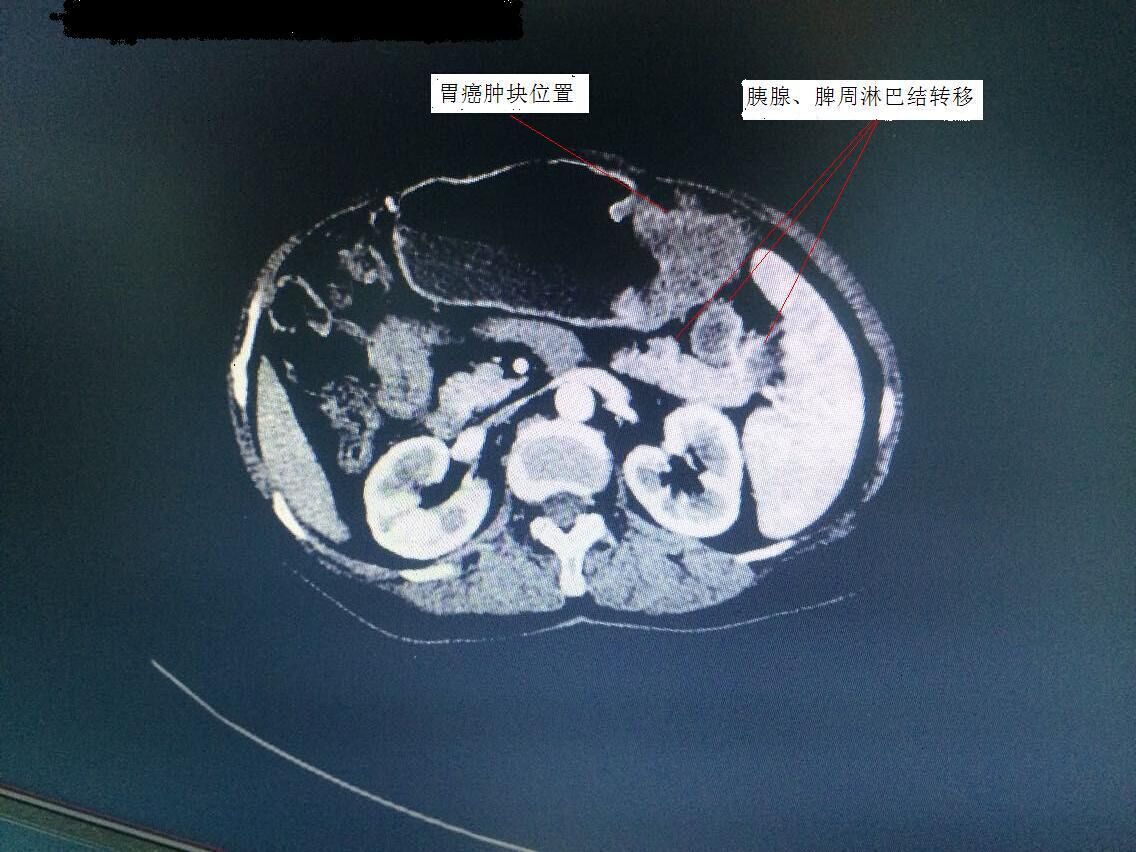

胃腸外科譚曙光主任率領(lǐng)科室團隊,術(shù)前對手術(shù)方案進行了仔細研究。該患者胃癌腫塊位于胃體,腫塊較大,且胰腺尾部、脾門等周圍淋巴結(jié)轉(zhuǎn)移(見圖1)。為保證治療效果,提高患者生存質(zhì)量,需行全胃、胰腺體尾部以及脾臟聯(lián)合切除。此等手術(shù)在以往傳統(tǒng)開腹方面均具有較高難度,若想在微創(chuàng)下完成切除,更是難上加難。經(jīng)過科室嚴密的探討,最終確定為該患者行腹腔鏡下微創(chuàng)手術(shù)。手術(shù)歷時3個小時,在手術(shù)室及麻醉科的配合下,順利完成衡陽市第一例腹腔鏡下胃癌根治聯(lián)合脾臟、胰腺體尾部切除術(shù)(術(shù)后標(biāo)本見圖2)。術(shù)后,該患者恢復(fù)良好,手術(shù)疤痕不到傳統(tǒng)手術(shù)的四分之一(見圖3),目前已開始術(shù)后化療。

圖1